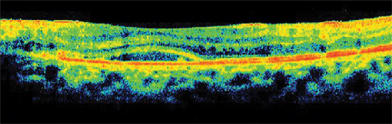

Figure 2. OCT of the right eye with macular edema and loss of the normal foveal contour.

At 1 month, our patient's vision was 20/60 with resolution of macular edema on optical coherence tomography (see Figures 4 and 5). Her CD4+ count improved to 102 cells/μL without evidence of IRU. She did not develop a retinal detachment, another vision-threatening complication of CMV retinitis. Based on several cases series, the US Public Health Service and the Infectious Diseases Society of America recommend discontinuation of anti-CMV treatment when the CD4 count is greater than 100 to 150 cells/μL for at least 6 months.7 Late relapses do occur, requiring continued monitoring.8

Figure 5. OCT of the right eye showing improved foveal contour and no macular edema after 1 month of treatment.